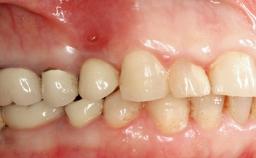

The fracture of an implant after it has been restored is one of the most severe complications. It most frequently occurs in partially edentulous jaws (1.5%). Most implant fractures involve implants with a diameter of 3.75 mm made of commercially pure titanium (Eckert 2010). Unfortunately, many cases are not reported or documented by the clinicians involved in resolving the problems created by the fracture. This case report describes the management of an implant fracture at site 36 in a middle-aged male patient. The implant had been restored with a screw-retained metal-ceramic crown.

Defining Characteristics One missing tooth to be replaced by an implant-borne crown

Mesio-Distal Space Anatomic space corresponding to the missing tooth +/- 1 mm

Inter-Arch Distance Ideal tooth height +/- 1 mm